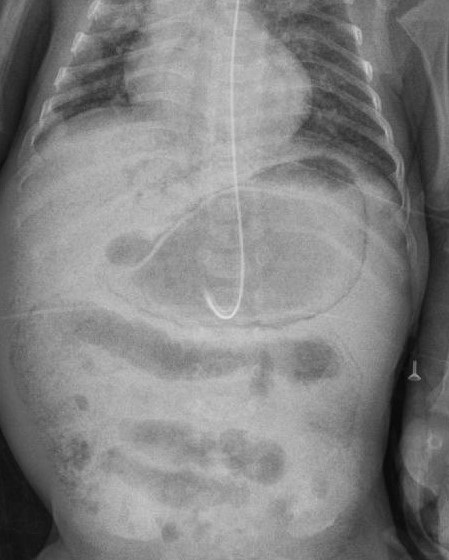

The baby responded to conservative management with antibiotics and withholding of feeds. Serial x-rays of the abdomen showed gradual resolution of the gastric pneumatosis (Fig. 2). Small formula feeds were reintroduced through the orogastric tube after 5 days and gradually graded up to full feed by Day 138 of life. The baby briefly required oxygen via nasal cannula at the time of developing gastric pneumatosis, which was weaned and stopped by day 133 of life and since then saturations were maintained in room air with stable hemodynamic status.

Figure 2

Follow-up X-ray of the abdomen showing resolution of gastric pneumatosis.